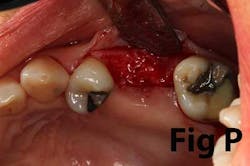

There is an abundance of literature showing increased gingival inflammation around natural dentition (exacerbated when a fixed restoration is present) when there is less than 2 mm AG. (Figs. 8, 9: post grafting) There is an abundance of literature showing increased incidence of peri-implant mucositis when there is inadequate attached tissue — a weaker connective tissue adhesion and lack of Sharpey’s fibers make the peri-implant tissue even more susceptible to bacterial challenge. (1-6, 8, 10) And as periodontitis is always preceded by gingivitis, peri-implantitis will be preceded by peri-implant mucositis. If we can decrease the incidence of peri-implant mucositis by providing a better and more resilient tissue phenotype, we can lower the incidence of peri-implantitis.The FGG procedure is indicated in cases of implant therapy where this is less than 2 mm of attached tissue present. Sometimes, a FGG is preferred over CTG because: (1) the FGG results in greater gain of attached tissue, (2) the FGG alleviates frenum/muscular pull whereas the connective tissue may increase muscular tension after the flap is coronally advanced, and (3) creeping attachment is often a positive byproduct of the FGG procedure.

Refer to Case Nos. 1 & 2.

Case No. 1